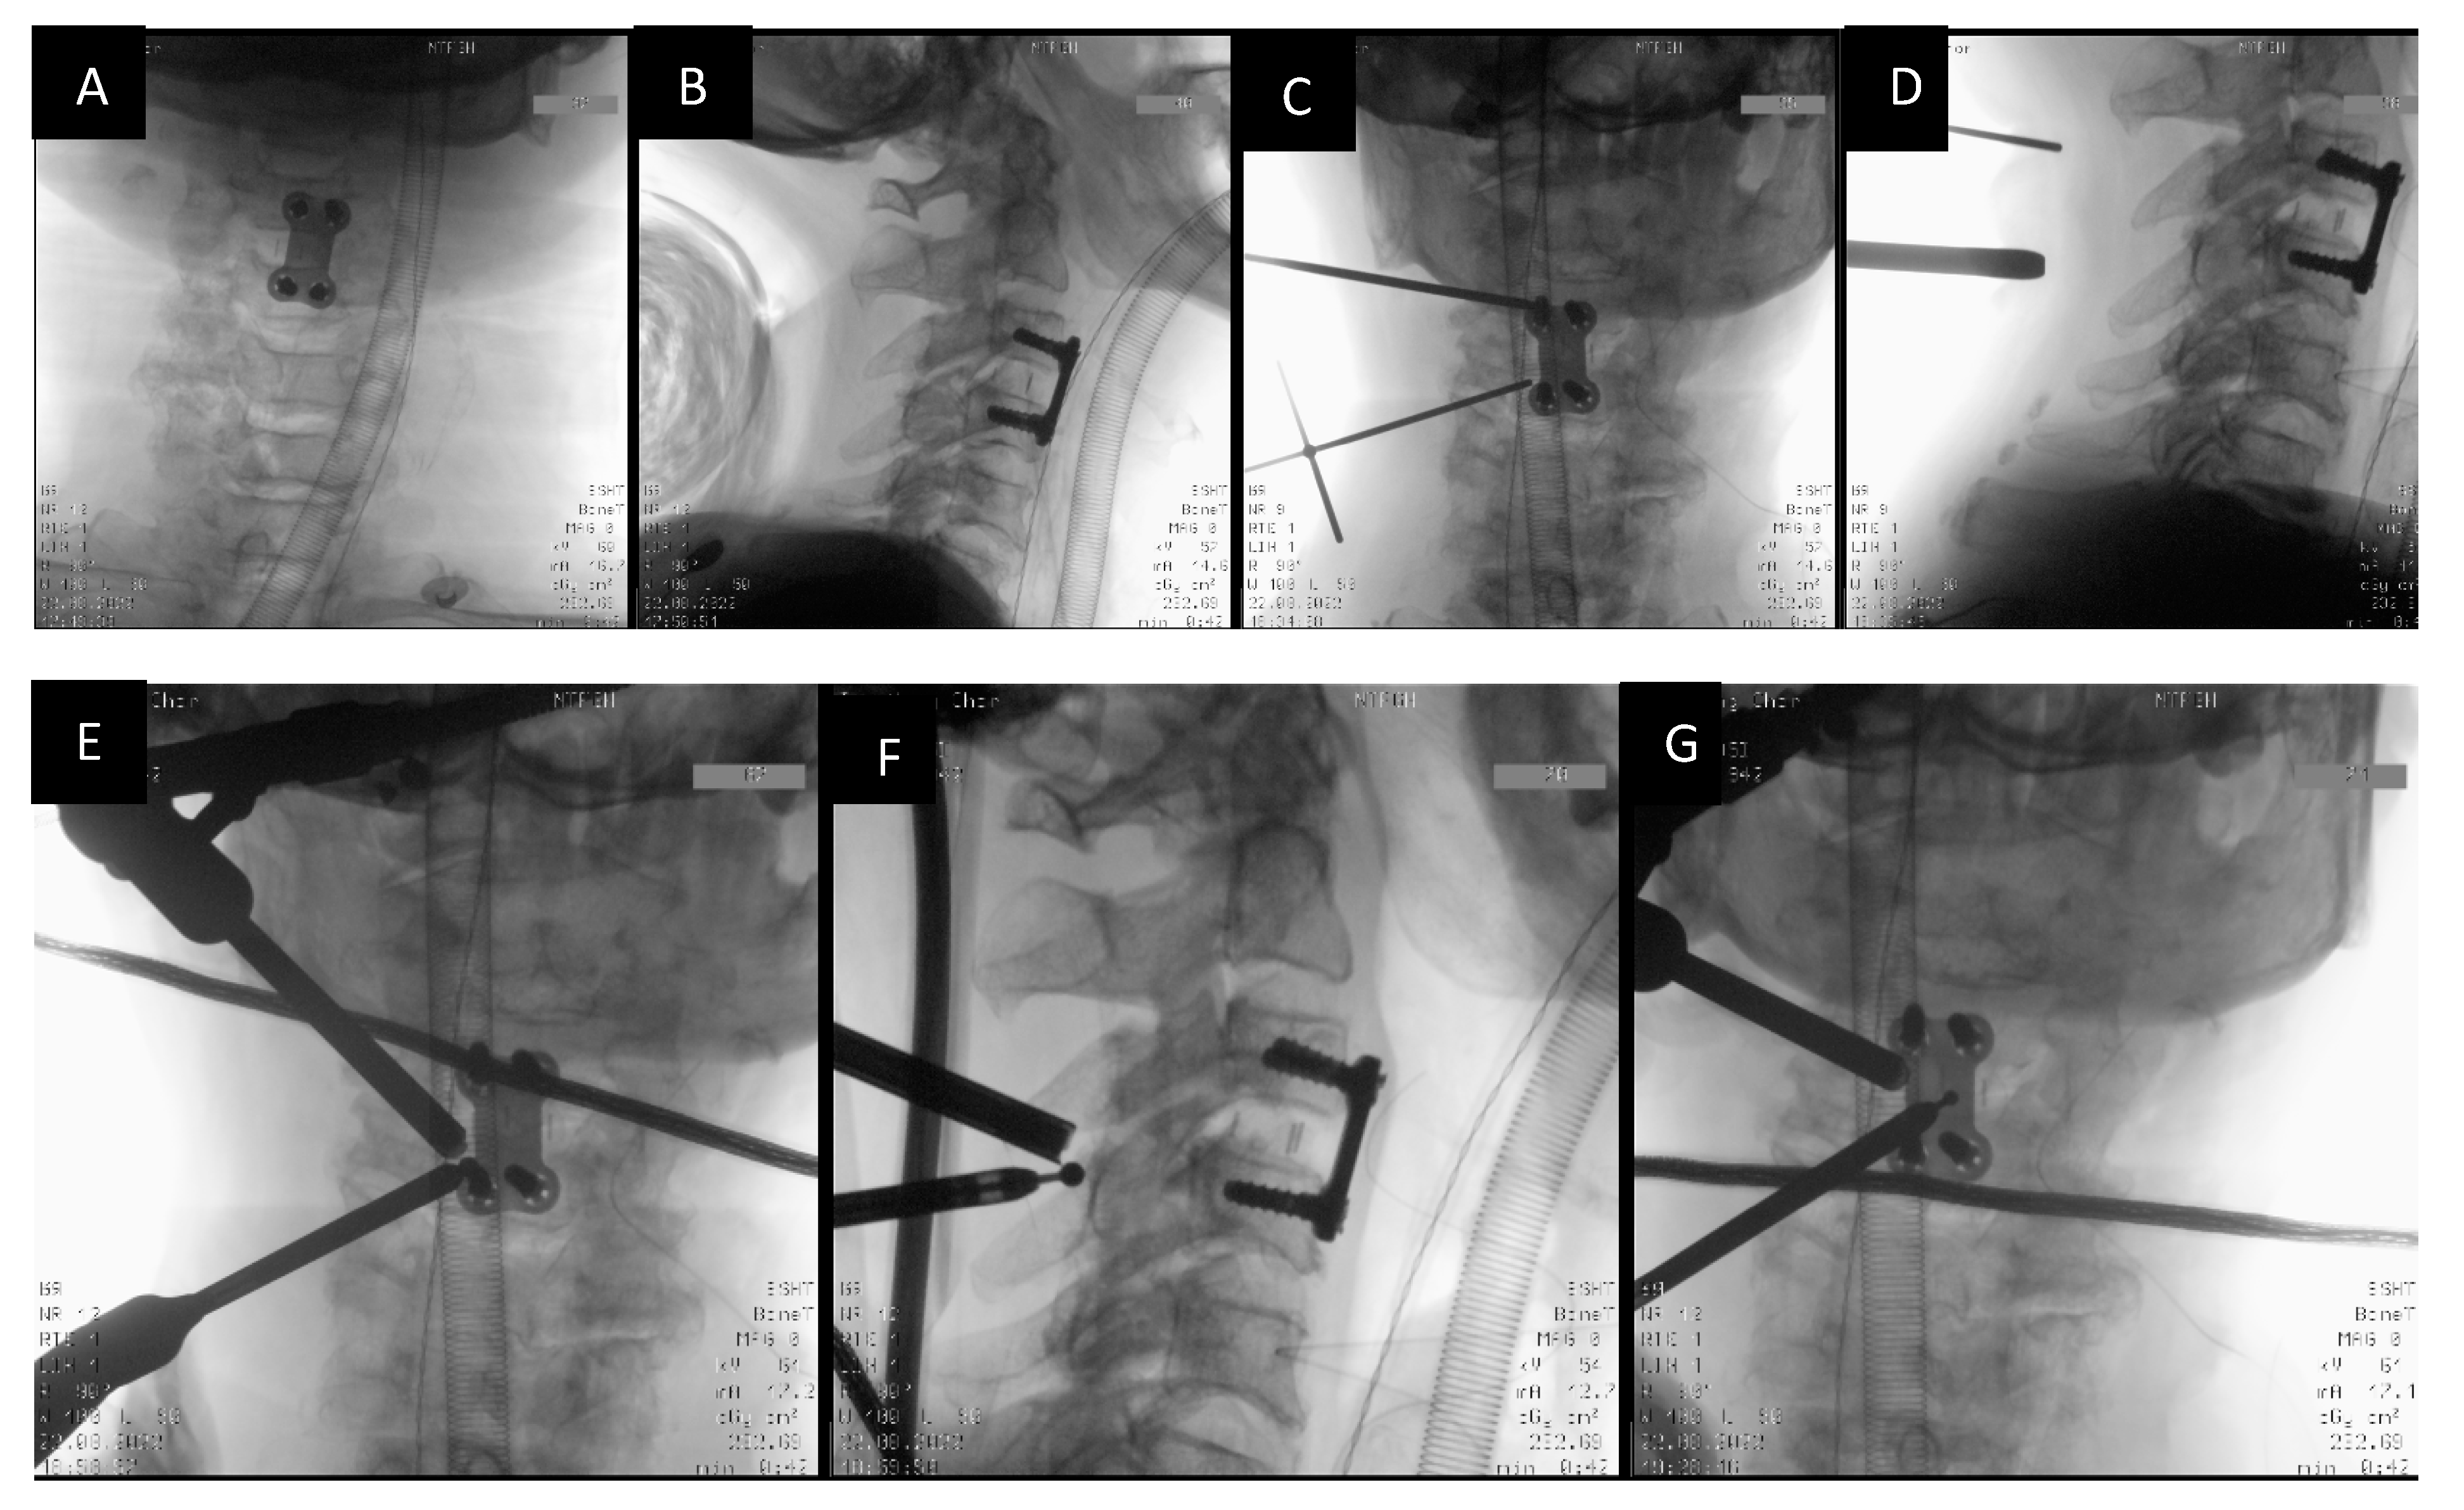

2.4. Docking and Working Channel Placement

- Usage of intraoperative fluoroscopy to localize the drilling and the extent of decompression.